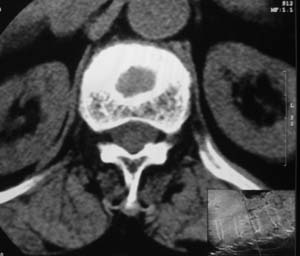

患者,女,72岁,胸背部疼痛3月余,无明显外伤史。曾应用局部封闭、非甾体类止痛药治疗效果不明显,近来疼痛缓解频感背困,平卧缓解,近日行ct检查发现胸12椎体病变,烦请同道发表意见,诊断什么?有何治疗经验!谢谢!!!

标绘图示:第十二胸椎级第一腰椎椎体楔形改变。ct扫描示:第十二胸椎椎体骨质结构紊乱,并可见一囊状低密度影,边缘可见硬化,椎体皮质完整。

考虑:第十二胸椎陈旧性骨折、许莫氏结节。